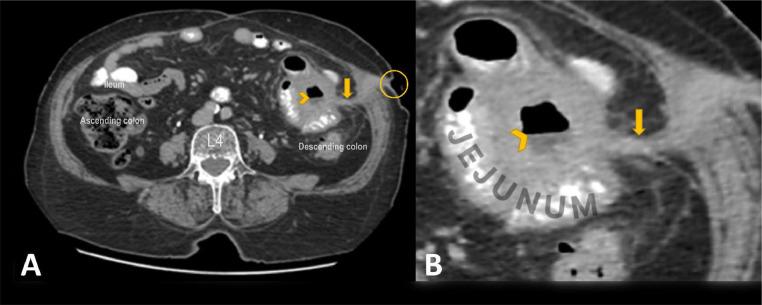

This case report highlights a minimally invasive approach to the management of enterocutaneous fistulas (ECFs), specifically jejunocutaneous fistulas (JCFs), using n-butyl cyanoacrylate (NBCA) glue. The patient, a 77-year-old female with Crohn's disease, presented with abdominal pain, fever, chills, and persistent discharge from the JCF site. Conventional treatment options for ECFs, ranging from conservative management to surgical intervention, are often associated with morbidity and prolonged recovery periods. This case demonstrates the successful closure of a JCF using NBCA glue injection, resulting in complete symptom resolution and sustained fistula closure at 18 months follow-up. The application of NBCA glue represents a promising alternative to traditional approaches, offering reduced procedural risks and shorter recovery times. This report highlights the role of minimally invasive techniques in the management of ECFs and highlights the need for further studies to establish standardized protocols and expand the clinical use of this approach.